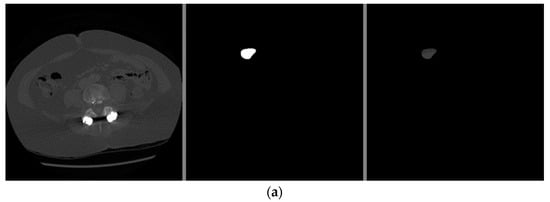

The visual examples of the results of the model for detecting liver cancer from the dataset are shown in Figure 7.

Figure 7.

The visual results of the first model for cancer detection on LiTS dataset: (a) normal case (no tumor detection); (b) abnormal case (tumor detection).

From the previous results mentioned in Section 3, it was observed that the first proposed method (the combination of DeeplapV3 and ResNet 50) achieved better accuracies than the second method (the combination of VGG-16, ResNet 50 V2, U-Net and LSTM) using both datasets. Therefore, we confirmed the first method to be our method. We also observed from the results that the first method obtained a high accuracy of 99.5% on small data (the case of the second dataset), which makes it more robust and efficient than other previous deep learning methods. In addition, when using the first dataset, as shown in Figure 7, it was observed that the first model could accurately detect cancer from the normal image. However, we can see from Figure 9 that the second model made some noise when detecting cancer from a normal image (as shown in Figure 9a). In terms of the second dataset (small data), we can observe from Figure 12 and Figure 16 that, when detecting cancer from the image, the two models detected cancer with some noise, but the first model was still better than the second model, with less noise. We employed the ReLU activation function in our models because it does not become active in all neurons at the same time. In addition, ReLU gives the highest accuracy, compared with other nonlinear activation functions, such as the Tanh activation function. Table 5 shows a performance comparison when using ReLU as an activation function and other nonlinear activation functions on the 3D-IRCADb-01 dataset.